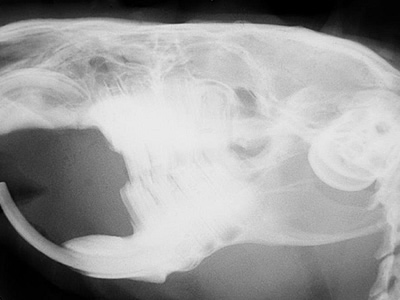

- Hier seht ihr das Röntgenbild eines Meerschweinchen-kopfes. (c) Dr. med.vet. Jochen Krüger www.tierzahn.de

- Spezielle Interoral-Röntgenfilme zum Röntgen des Tieschädels und einzelner Zähne